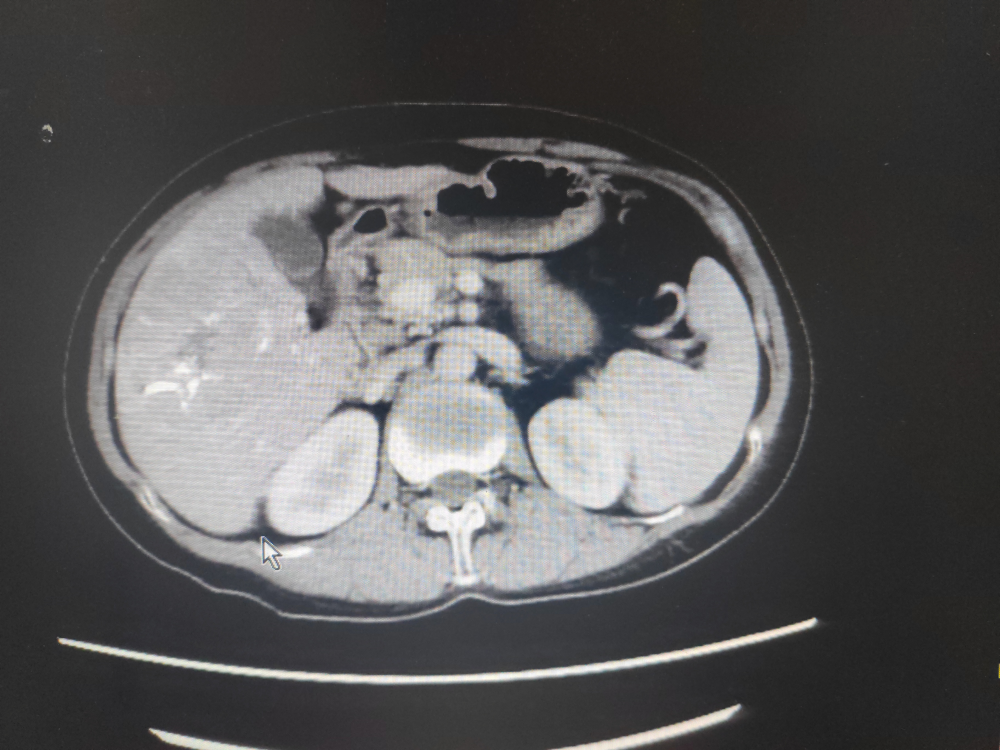

2022年3月7日上腹部增強CT